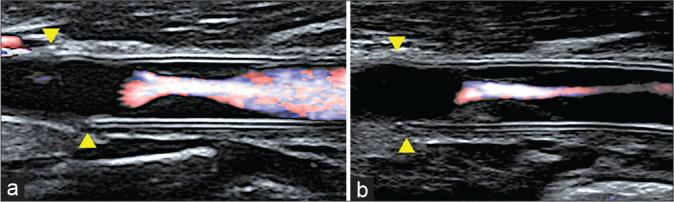

A woman in her 20s experienced injury to the right carotid artery during an operation for removal of a carotid body tumor 6 years before presentation. The right common carotid artery and internal carotid artery were replaced with an artificial vessel graft at that time. Intraluminal stenosis in the graft was not identified 3 years after surgery; however, 4 years after surgery, stenosis was recognized at the non-anastomotic site inside the artificial vessel graft. Subsequently, antiplatelet therapy was initiated. The stenosis was noted to progress gradually in follow-up appointments. Therefore, we decided to intervene because of the patient's young age and the risk of long-term hemodynamic stress. Angiography revealed pseudo-occlusion in the artificial vessel. Percutaneous transluminal angioplasty was performed for stenosis with distal protection; subsequently, CAS was performed. The patient was discharged without neurological deficits 4 days after the operation, and no apparent restenosis was observed as of the 1-year follow-up.